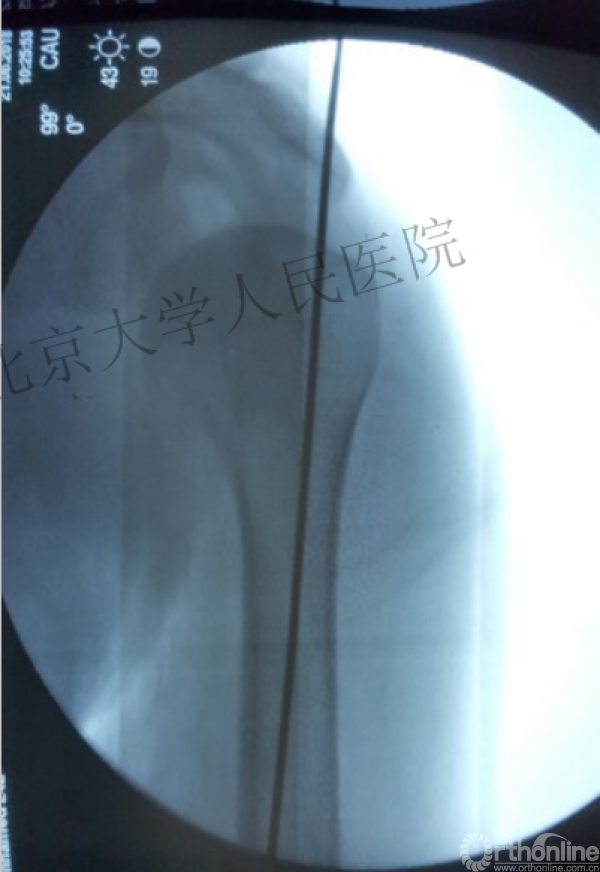

克氏针的应用“joystick”

简单骨折的闭合复位技术:以克氏针作为“joystick”

髓内钉的应用复位是关键